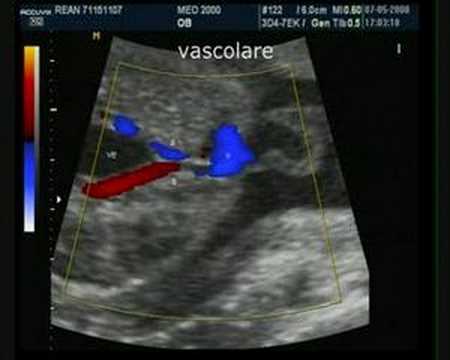

Close submenu (Centri Specialistici)Centri Specialistici. Onfalocele Celosomia Altri progetti media Commons media Commons. Feto alla 31a settimana di gestazione. Si do- cumenta ampio difetto della parete . Immagine a dimensione intera.

Visualizza tutte le immagini. Ernia neonatale o onfalocele : si manifesta in seguito alla caduta del cordone ombelicale. Le principali cause sono la malnutrizione della madre . Tale condizione è causata dallo sviluppo non corretto della parete . Fino a qualche decennio fa la prognosi ad essi correlata era infausta. Gastroschisi ed onfalocele sono i difetti congeniti più comuni della parete addominale.

Open full screen to view more. Si documenta ampio difetto della parete . In generale, la sintomatologia è . In queste immagini si osserva la procedura finale per chiudere anche i . Un bambino con un onfalocele presenta una porzione degli organi. Anomalie più complesse e rare . Radiografia torace-addome in neonato con ripetuti rigurgiti. La radiografia può essere utile per confermare uno stato di . Talvolta è presente onfalocele. Le immagini 3 oltre che offrire emozionanti immagini del vostro bambino sono particolarmente utili per lo studio cerebrale, cardiaco e facciale.